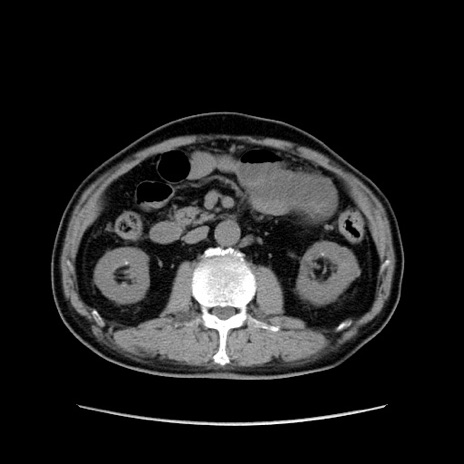

矢状断像